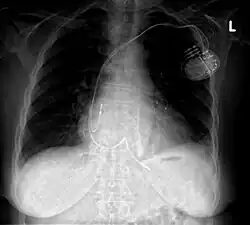

- Intrakardiale Stimulation durch Implantat: Der Herzschrittmacher wird oberhalb der rechten oder linken Brust unterhalb des Schlüsselbeines zumeist unter die Haut (subkutan) oder bei hageren Patienten unter den großen Brustmuskel (submuskulär) implantiert. Die Elektroden werden transvenös zum rechten Vorhof oder rechten Ventrikel geführt (beim biventrikulären Schrittmacher wird eine dritte Elektrode über den rechten Vorhof und den Koronarvenensinus zur Posterolateralwand des linken Ventrikels vorgeschoben). Diese Art der Implantation eines Herzschrittmachers ist die in der Praxis am häufigsten angewendete.

Biventrikulärer Herzschrittmacher

Zur kardialen Resynchronisationstherapie (CRT) wird geraten bei asynchronem, kardialem Kontraktionsablauf, meistens im Rahmen eines Linksschenkelblock, und gleichzeitig hochgradig eingeschränkter Pumpfunktion mit symptomatischen Verlauf[61], das heißt die eine eingeschränkte kardiale Belastbarkeit des Schweregrades II, III oder IV nach NYHA-Klassifikation mit sich führt.[62] Es konnte eine Verbesserung der kardialen Pumpfunktion, der körperlichen Belastbarkeit, der Lebensqualität und des Überlebens, insbesondere in Kombination mit einer Funktion als Implantierbarer Kardioverter-Defibrillator, belegt werden. Hierzu wird eine dritte Elektrode venös über den Koronarvenensinus in Höhe der Seitenwand (posterolateral) der linken Herzkammer eingebracht. Beim Linksschenkelblock kontrahiert sich zuerst die Kammerscheidewand (Septum) und verspätet die Posterolateralregion, was zum ineffizienten Pendelfluss innerhalb der Herzkammer führt und erheblich zu einer reduzierten Auswurfleistung beitragen kann. Durch die vorzeitige Stimulation der verspätet erregten Posterolateralwand kann der gestörte ventrikuläre Kontraktionsablauf wieder resynchronisiert werden.